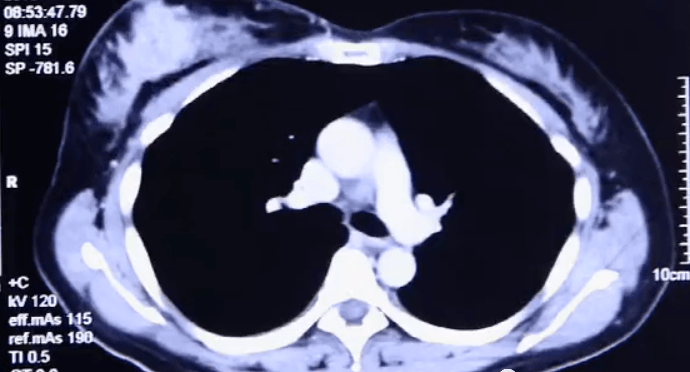

来自印尼Mary曾因左乳的小结块去当地医院检查发现自己患上乳腺癌 。 为了免受传统手术开刀之“苦”,Mary来到我院就诊 。 入院后检查发现Mary的乳腺癌组织直径已从2.2cm扩大至6cm,专家团队经过会诊最终确认了其治疗方案——冷冻消融治疗 。

文章图片

超声引导下将探针插入肿瘤区内,当温度下降超过一定水平时,冰晶开始在肿瘤细胞内部形成,冻结供应营养的血管,停止运输养分,摧毁肿瘤细胞组织 。 持续几分钟后,迅速又复温 。 经过这样两个循环后,肿瘤病灶完全被“冻结”,进而达到治疗效果 。 由于病灶位置浅,离皮肤较近,因此在术中还要对皮肤采取保护措施,以免冻伤皮肤 。